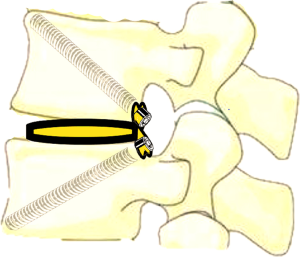

In ETDIF/PT-Endo-LIF technique, percutaneous pedicle screw implantation uses different approach from interbody decompression and fusion. Moreover, decompression and fusion are often accomplished by setting a 14-mm channel additionally. Decompression, interbody fusion and percutaneous pedicle screw implantation are not completed in a single 7.5-mm channel. PETOFPC overcomes the above limitations, and realizes one-stop decompression, fusion and fixation in a single 7.5-mm channel (Figure 16). The implementation of this technique requires the participation of a new integrated fixable and fused interbody cage (Figure 17).

PETOFPC technique innovatively sets screws from posterior corner in lumbar spine in a regular 7.5-mm diameter channel. PETOFPC is also performed in the posterolateral transforaminal approach (Figure 18). A cylindrical sheath with an outer diameter of 7.5 mm were inserted in sequence. Through the sheath alone or the endoscope, the intervertebral disk and cartilaginous endplate were removed while confirming through percutaneous endoscopic observation that no cartilage remained. At the completion of the endplate preparation, the new integrated fixable and fused interbody cage was inserted into the intervertebral space (16). Before the new integrated fixable and fused interbody cages were expanded, we should clearly expose the screw entry point in posterior corner. The screw entry point is the bony area between the pedicle and the endplate. When intervertebral height was restored, the two wings of new integrated fixable and fused interbody cage splay to the sides and fit to posterior corner in lumbar spine (Figure 19). In the single 7.5-mm channel, endoscopic visualization was used to monitor placing screws to make the new integrated fixable and fused interbody cage fixed in lumbar spine. The angles of screw placement were made up of inward inclined angle, head tilt angle and tail tilt angle, namely c1, c2, c3, a1, a2, a3, b1, b2 and b3, all which was measured and analyzed in this study.

In this article, we preset six paths as screw trajectory of oblique fixation from posterior corner in lumbar spine, namely, PA, PB, PC, PD, PE, and PF (Figures 3,4). The design of the pathway is determined by the technical characteristics of spinal endoscopy in clinical practice, considering simultaneously the biomechanical properties of the screw, the longer bone canal and more cortical penetration. The paths should be neither penetrating into the intervertebral space nor making the anterior large vessels injured. Considering the above factors, PE path should be the optimal (longest) path for oblique fixation from posterior corner in lumbar spine.

PE path was the longest in all the paths for oblique fixation from posterior corner in lumbar spine, with an average length of 45.95 mm, which was significantly longer than other paths in the same vertebral body (Figures 10-12). Its upward path first increases and then decreases, reaching the highest point at L3 (46.76±2.88 mm). Its downward path first decreases and then increases, with the lowest decline at L5 (45.66±3.21 mm) (Figure 20). At the same time, the fixed angles (a2, b2, c2) of the PE path in sagittal and axial planes are between a1-a3, b1-b3, and c1-c3, which may neither penetrate into the intervertebral space nor injure the anterior large vessels. Therefore, the PE path is safe and easy to grasp in theory.

In addition, the pullout strength of PE path is greater because the bone canal was across the entire vertebral body from the posterior (upper and lower) corner of one side in lumbar spine oblique to the anterior (lower and upper) corner of the contralateral side in lumbar spine. The PE path is considered to be the optimal one for oblique fixation from posterior corner in lumbar spine.